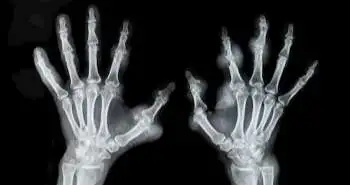

The relationship between autoantibody status and treatment response to methotrexate (MTX) remains unclear in RA. The researchers aimed to find an association between autoantibody status and early remission in recently diagnosed RA patients treated with MTX using real-world data.

International observational database (METEOR) was utilized to screen RA-patients initially treated with MTX. Patients were divided  into autoantibody negative (RF- and ACPA-negative ) and autoantibody-positive (RF- and/or ACPA-positive) groups. Cox-proportional hazards regression was used to estimate the impact of autoantibody status on the chance of attaining remission within 3 to 6 months.

For analysis, data from 1826 RA patients were available. In 17% (318/1629) patients, DAS remission was achieved. For autoantibody-negative and positive patients, DAS remission was found to be similar. That is why; there was no connection between autoantibody positivity and remission [hazard ratio (HR) 0.89, 95% CI 0.57, 1.38]. Similar findings were found when stratified for combination treatment (HR 0.76, 95% CI 0.37, 1.54) or MTX monotherapy (HR 0.75, 95% CI 0.41, 1.37). In 33% (530/1590) of all patients, good physical function (HAQ < 0.5) was noted. Also, there was no relation between autoantibody-positivity and HAQ < 0.5 (HR 1.05, 95% CI 0.71, 1.57).

No significant relationship between autoantibody status and early remission in newly diagnosed RA-patients receiving MTX has been observed in the present study. This indicates that MTX is useful as an initial treatment strategy regardless of autoantibody status.